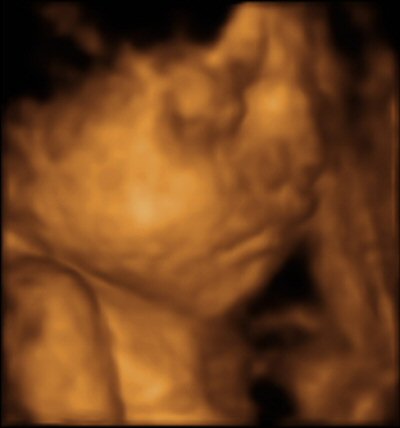

- 29 week 4D scan

- The scan photos shown below are 3D images from the babybond 4D scan at 29 weeks gestation.